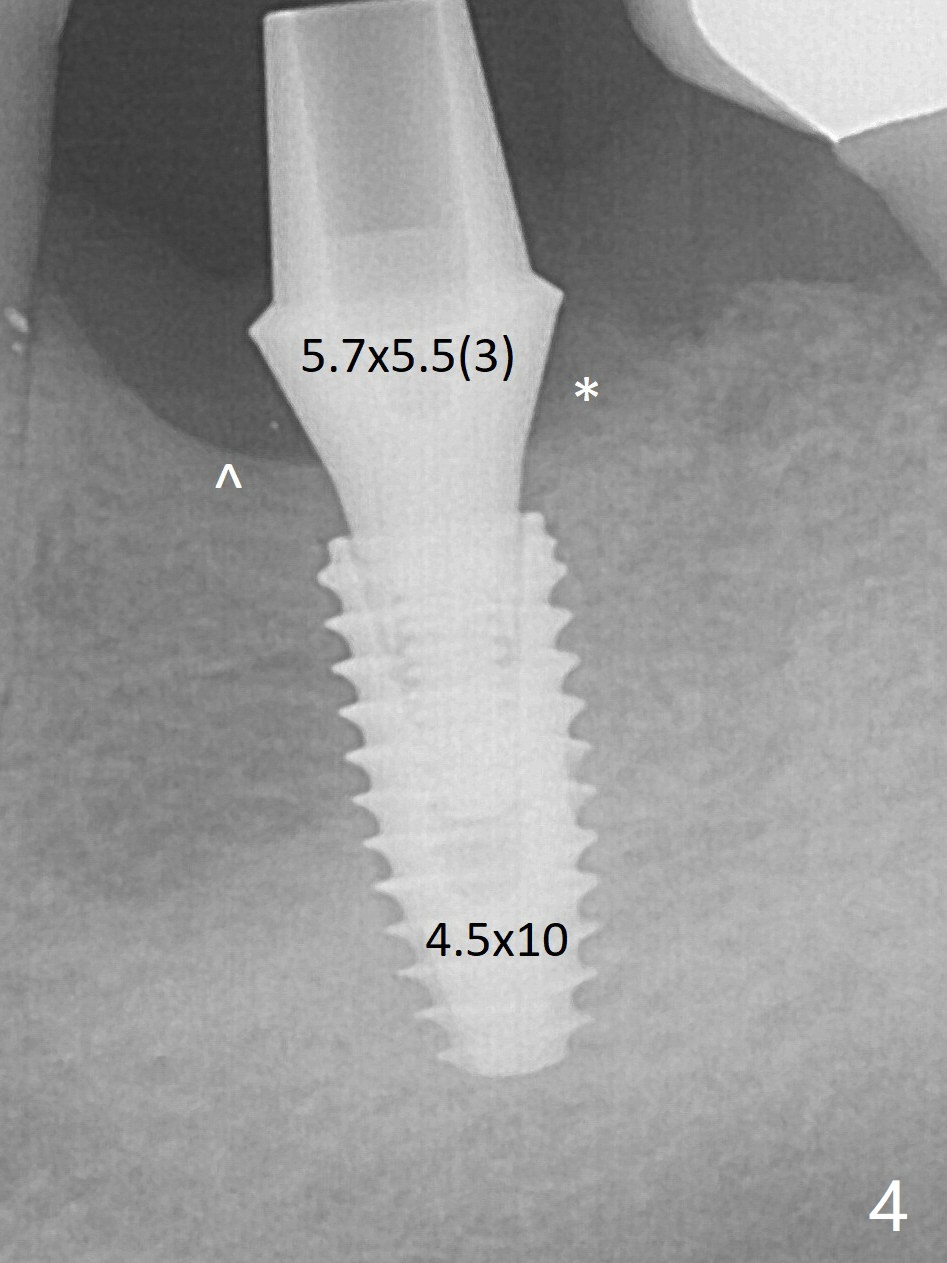

With the final implant (4.5x10 mm, Fig.4) being placed deeper to close the apical space, the cuff of the final abutment increases by 1 mm.  Autogenous bone is used to pack around the implant distobuccally (*).  Although the implant seems to be placed significantly apical to the lingual crest (^), it is at the buccal crest.  There seems to be no bone loss 3 months postop; impression is taken (Fig.5).  When the crown/abutment at #30 is loose 2nd time 1 year 7 months post cementation (Fig.8 taken post retightening), the screw at #19 fractures.  The tooth #2 needs a crown.  The patient cannot use the anterior teeth, since the teeth #8 and 9 have root fracture.  Can extraction and bone graft increase bone height?